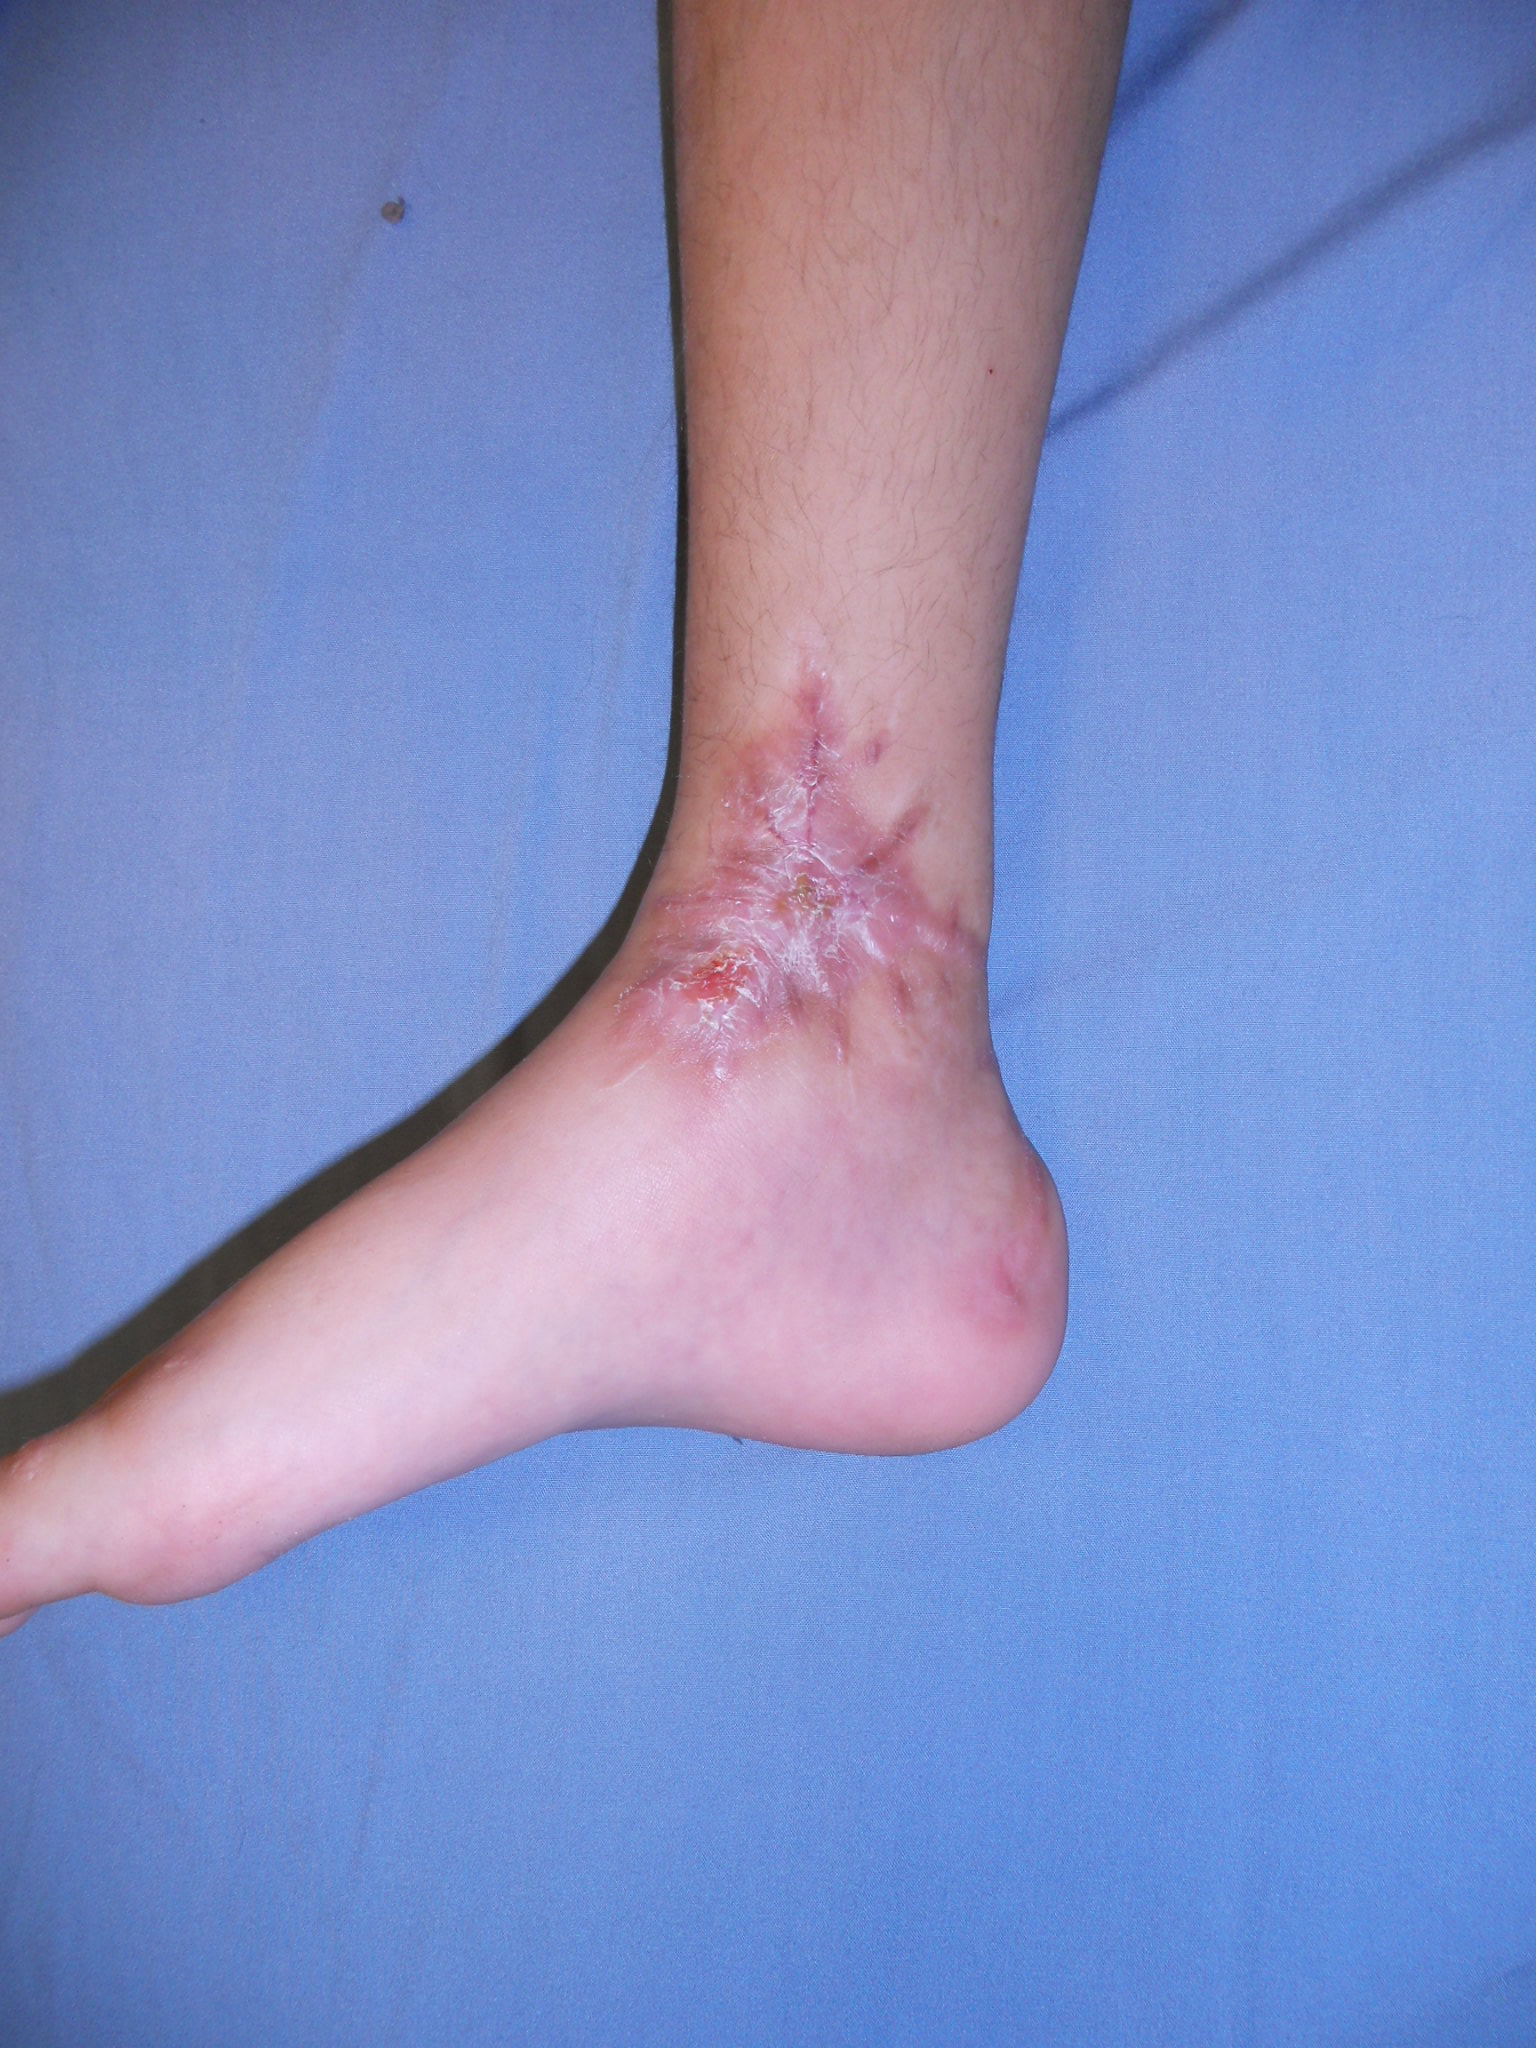

Fracturas fisarias Salter-Harris VI de tobillo y pie. [Salter-Harris VI fractures of the foot and ankle.]